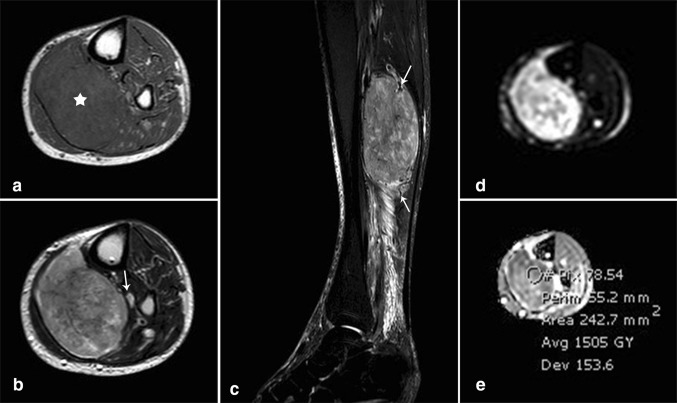

MR imaging (Fig. 2) of the left leg was then performed on 1.5 T magnet (Philips Ingenia, Eindhoven, The Netherlands) and showed a large 12 × 7.3 × 5.8 cm soft tissue lesion within the soleus muscle which had isointense signal on T1-weighted images (Fig. 2a) and appeared heterogeneous on T2-weighted images showing variable signals (Fig. 2b). The mass was compressing the posterior tibial neurovascular bundle and displacing it anteriorly. Sagittal STIR images (Fig. 2c) showed similar signal to that seen on T2-weighted images along with peripheral prominent flow voids. The lesion showed areas of high signal intensity on diffusion-weighted images (Fig. 2d) and low signal intensity on ADC map (Fig. 2e) consistent with impeded diffusion. The mean ADC value was 1.5 and the minimum ADC value was 1.1. Intravenous gadolinium was not administered due to the patient’s kidney status.

Fig. 2.

MR imaging. (a) Axial T1-weighted (TR/TE = 532/20): large tumor (star) involving the soleus muscle at the proximal posterior leg compartment. The tumor is relatively isointense to the surrounding muscles. (b) Axial T2-weighted (TR/TE = 1205/100): heterogeneous tumor with areas of low, intermediate and high signal intensity. The tumor is abutting the posterior tibial neurovascular bundle (arrow). (c) Sagittal short-tau inversion recovery (STIR) (TR/TE = 7380/60): The tumor shows signal intensity similar to that seen on T2-weighted sequence. Multiple flow voids are noted at the periphery of the tumor corresponding to prominent vascularity (arrows). Note the presence of reactive edema in the surrounding muscle fascicles and deep fat planes, distally. (d, e) Axial diffusion-weighted images (d) (b = 900) and corresponding ADC map (e) showing heterogeneous SI of the tumor with mild restriction, mean ADC = 1.5 (range for malignancy: 0.7–1.2)